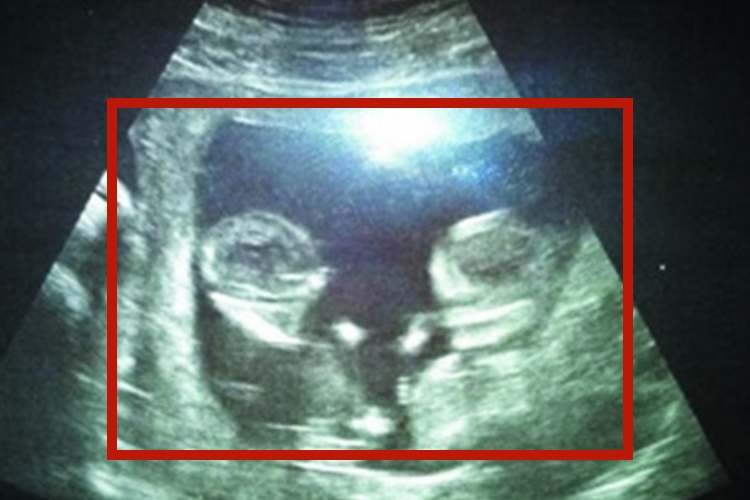

同卵和异卵B超的影像表现存在区别,具体如下:

同卵:同卵B超可见受精卵形成的两个胎儿共有1根脐带,其胎盘和胎囊则根据受精卵分裂时间不同而有所差异;两个胎儿常共用同一胎盘,两个胎囊的间隔有两层羊膜,两者血液循环相通。约有1/3的单卵双胎的胎盘胎膜与双卵双胎相同,但血液循环相通。